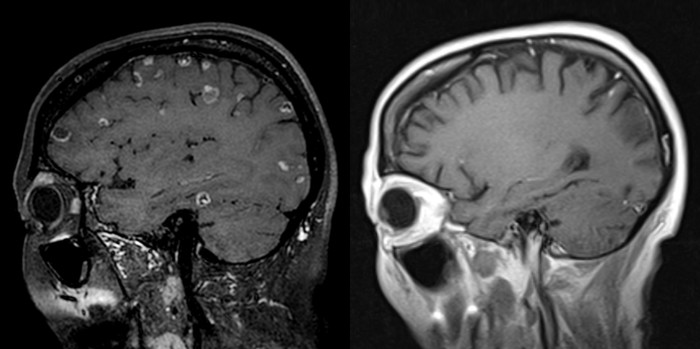

| ▲ 명역항암치료 및 표적치료 후 뇌로 전이된 암세포들이 모두 소멸됐다. |

결과는 놀라웠다. 암세포가 치료에 반응을 보이기 시작하더니 뇌와 폐에 있던 종양들이 약 10개월에 걸쳐 모두 사라졌다.

1개월 시한부 선고를 받은 말기 암환자가 거의 완치수준의 기적이 일어난 것이다.

최 교수는 환자의 여러 가지 검사 영상을 확인한 결과 10여 개가 넘는 암 덩어리들이 뇌 속 군데군데를 차지하고 있어, 서울에서 치료를 포기했다는 말을 실감할 수 있었다.